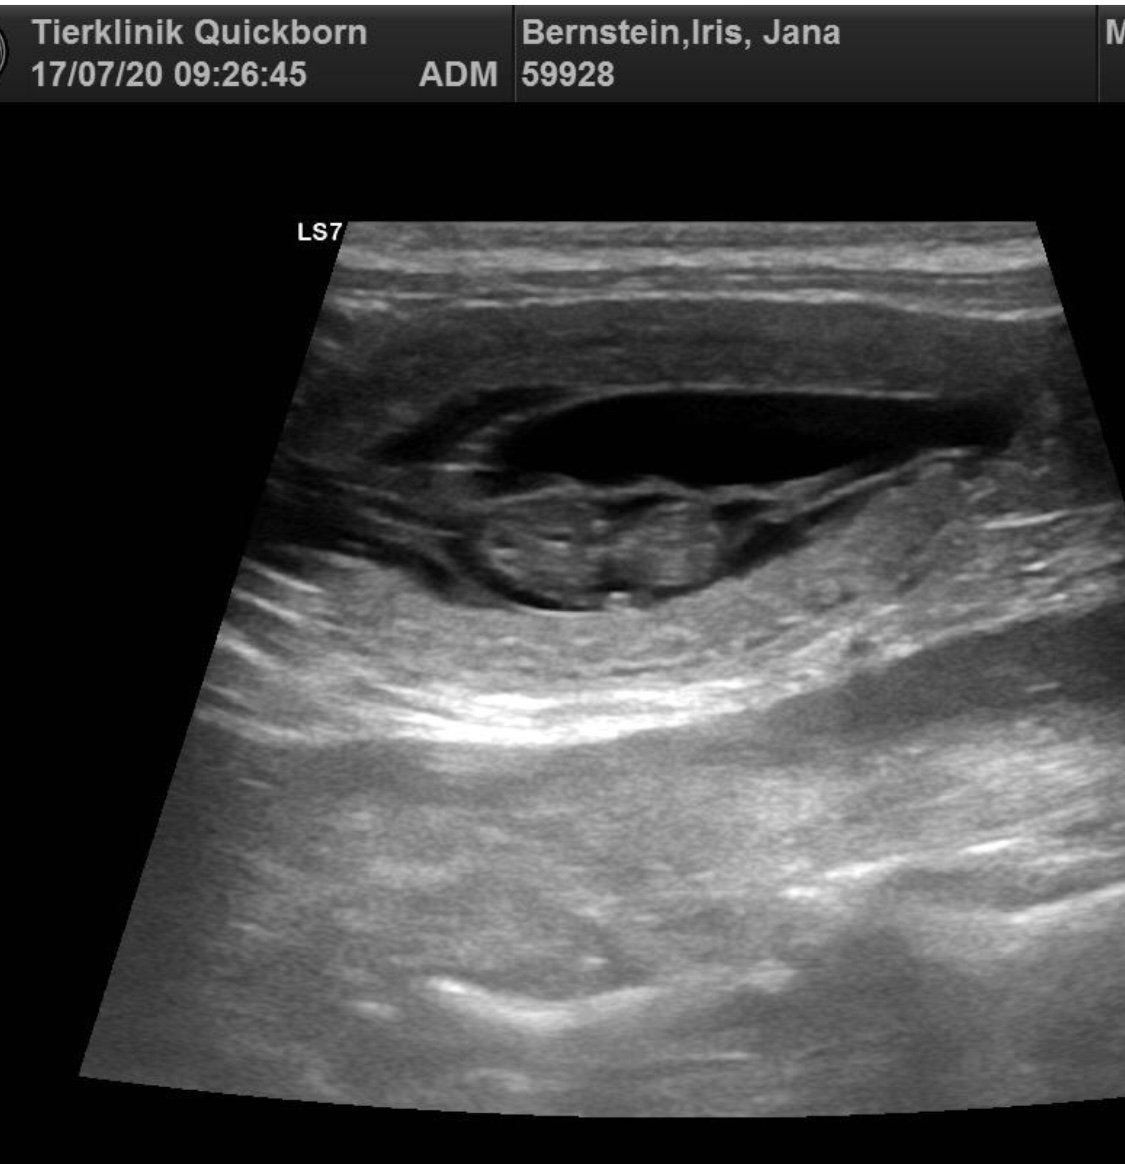

17.07.20 Jana ist trächtig 🥰 Im Ultraschall waren 4-6 Fruchtanlagen zu erkennen, allerdings können es auch mehr sein bzw. einige wieder resorbiert werden, daher kann keine echte Aussage zur Wurfgrösse gemacht werden, ausser dass es keine Einfrüchtigkeit ist. Jana geht es prächtig und wir freuen uns schon auf den Familienzuwachs! Stichtag ist der 20.08.20